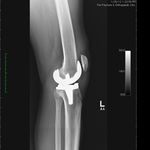

Bilateral Total Knee Replacement was recommended, and performed on July 27th 2011. Since surgery, the patient has made good progress and can now mobilize with the aid of a walker.

His x-rays and clinical examination suggest good early outcome with a fully mobilized patient with pain free knees and the ability to walk independently.